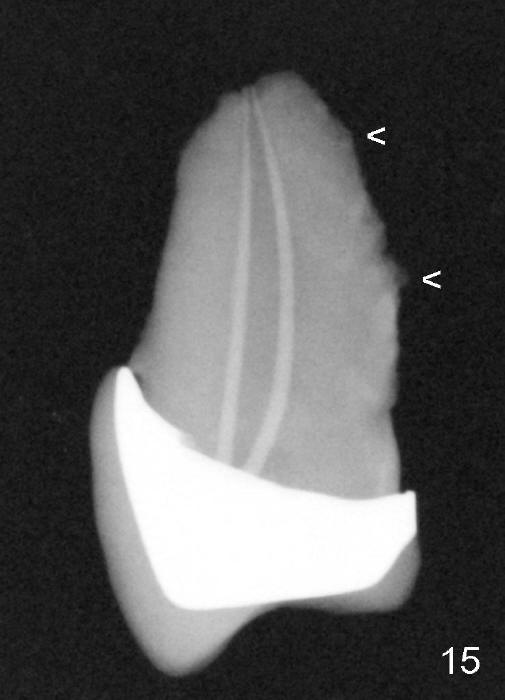

Exam of the extracted tooth shows that loss of the tooth is more likely due to periodontitis (Fig.14) than endodontic lesion (Fig.15).